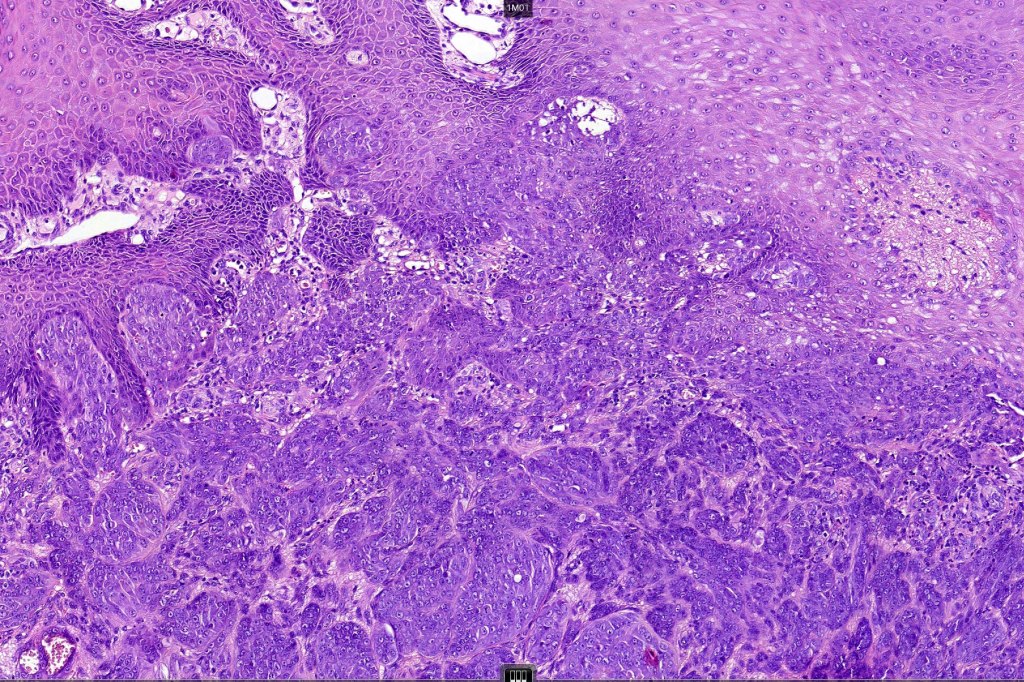

Histological features

•>5-10 mm

•Involve deep dermis or subcutis

•Asymmetrical, poorly circumscribed

•May show effacement/consumption of epidermis or ulceration

•Peripheral Pagetoid spread

•Large nodules which often show impaired maturation

•Loss of gradient with HMB45 and Ki67

•>20% Ki67 expression

•TERT promoter & PTEN mutations

•DNA copy-number variations